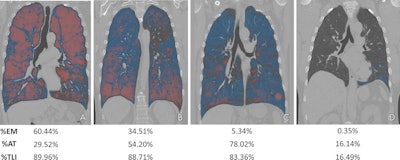

Visualization of lung involvement using attenuation difference maps and emphysema. (A) Image in a 66-year-old man with a 35-pack-year smoking history (Global Initiative for Chronic Obstructive Lung Disease [GOLD] stage 4, forced expiratory volume in 1 second [FEV1] = 23.8% predicted; FEV1/forced vital capacity [FVC] ratio = 0.32). (B) Image in a 61-year-old man with a 40-pack-year smoking history (GOLD stage 4, FEV1 = 12.9% predicted, FEV1/FVC ratio = 0.29). (C) Image in a 78-year-old man with a 65.8-pack-year smoking history and chronic bronchitis (GOLD stage 2, FEV1 = 59.6% predicted, FEV1/FVC ratio = 0.47). (D) Image in a 48-year-old man with a 26-pack-year smoking history (GOLD stage 0, FEV1 = 92.9% predicted, FEV1/FVC ratio = 0.82). %AT = percentage air trapping, %EM = percentage emphysema, %TLI = percentage total lung involvement. Images and caption courtesy of the RSNA."Most notably, we found that patients with moderate spirometric impairment and moderate-to-severe disease at CT had the highest likelihood of progression," wrote Kyle Hasenstab, PhD, of the University of California, San Diego and colleagues. "These results point to the synergistic value of CT and functional testing to identify patients at highest risk of progression and to potentially identify those who might derive the greatest benefit from medical or behavioral intervention to address ongoing tobacco exposure or other inhalational exposures."